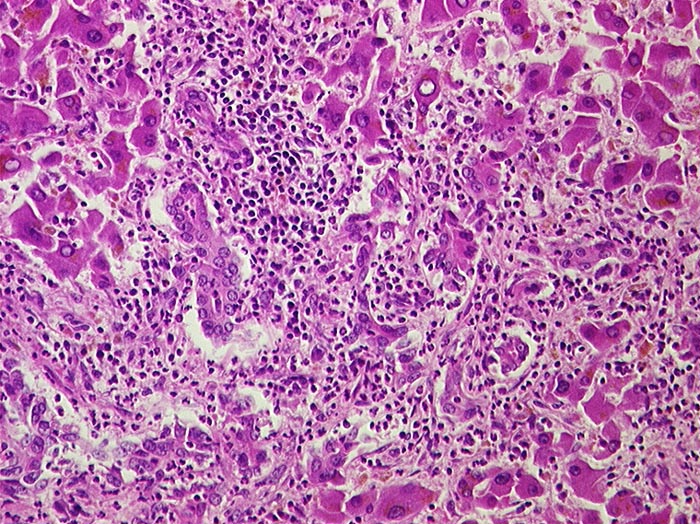

Eitrige Cholangitis

Portalfeld in der unteren Bildhälfte mit dichtem granulozytärem Entzündungsinfiltrat, welches auf die Gallengänge übergreift.

Metastasierendes Pankreaskarzinom mit Tumorbefall von Ductus choledochus und cysticus.